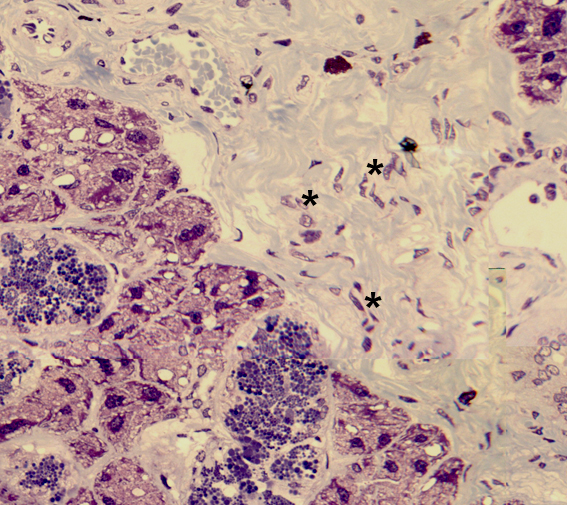

¿A qué tipo celular corresponden los núcleos marcados con asteriscos?

¿A qué células corresponden los núcleos marcados con asteriscos?